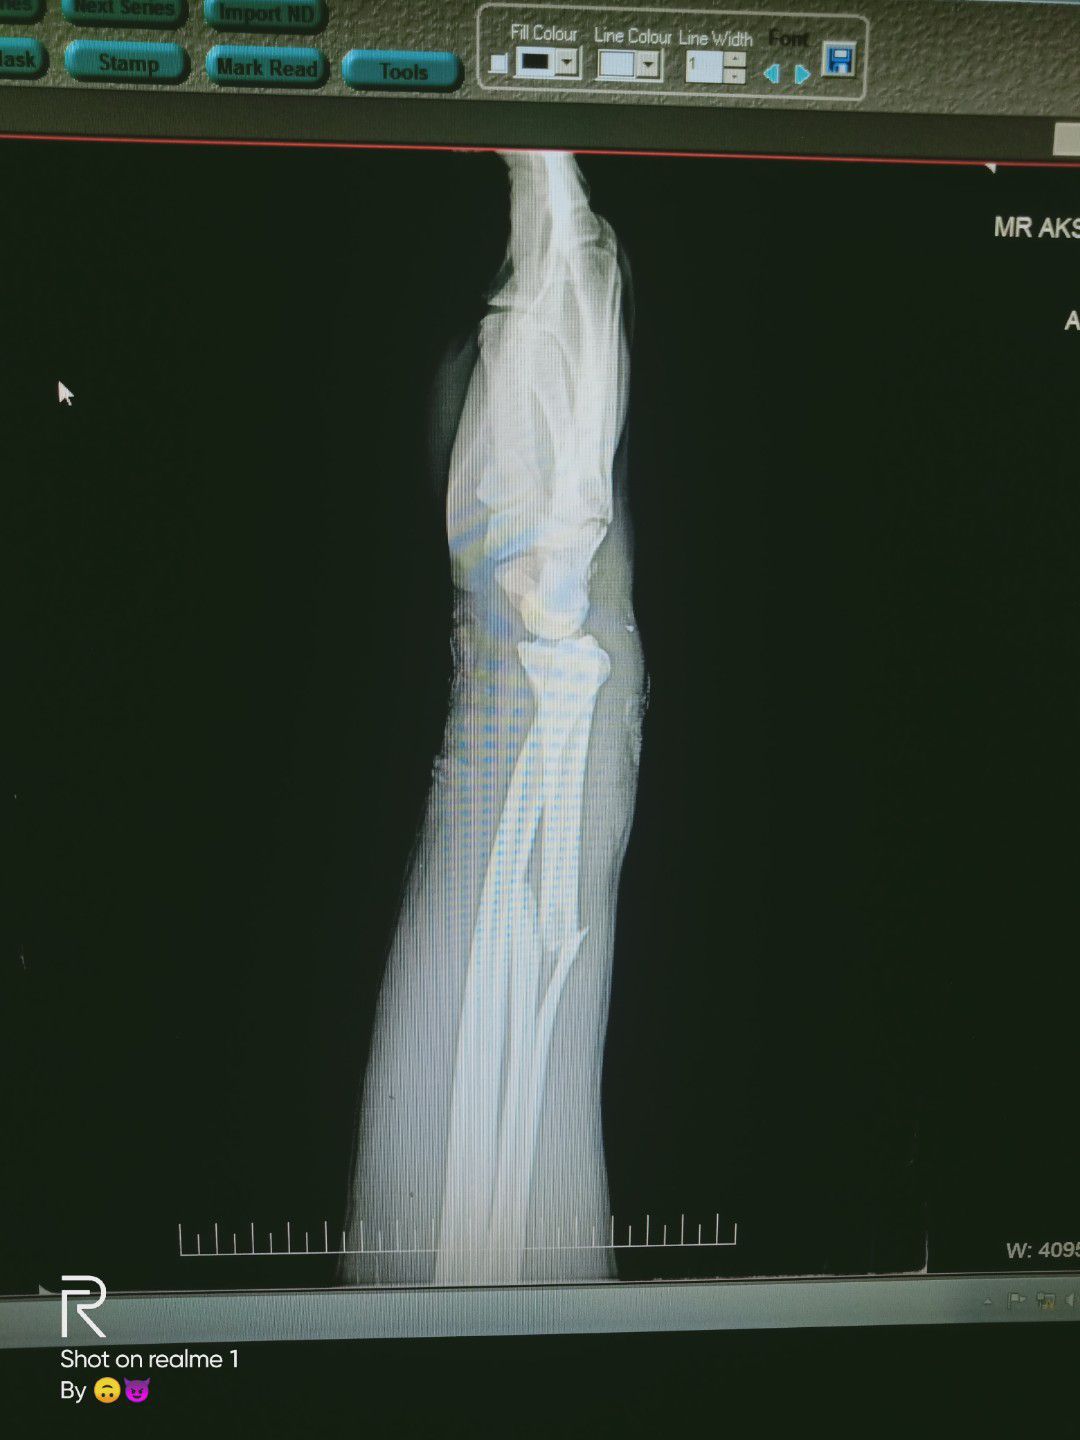

Radial bone

Fracture

Wrist

Upper